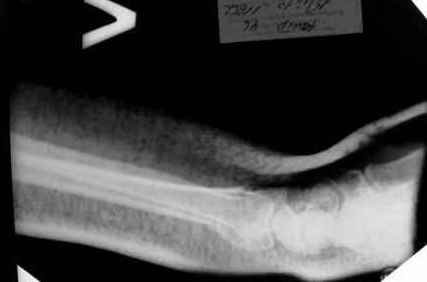

Уважаемые коллеги.Прошу обсудить случай лечения перелома дистального метаэпифиза лучевой кости. Ситуация скандальная и крайне неблагоприятная. Больная с патологической обстоятельностью мышления, склонностью к сутяжничеству, патологическими умозаключениями, не поддающимися коррекции (см. психиатрию, правда офиц. диагноза нет). В данном случае есть ряд ошибок с нашей стороны, прежде всего в отношении качества ведения документации (за что получил административное взыскание, по делом мне дураку). В остальном- придерживались в лечении подхода классический советской школы. Так как умную операцию…… сами знаете… 15.12- перелом луча в Москве. Там же репозиция, гипс. Дальнейшее лечение у нас в ЦРБ. 20.12.- вторичное смещение в гипсе21.12- под внутривенным наркозом- репозиция, гипсовая лонгета. Дальше начинается самое интересное. После репозиции больная заявила, что я (репозицию делал я) порвал ей все связки в суставе, посинел у нее 5 палец, якобы я за него тянул и т. д. На самом деле на 2 сутки после репозиции рука немного отекла и было незначительное сдавление гипсом, который был ослаблен. Дальнейшее лечение консервативное. Через 6 недель- гипс снят, назначено ЛФК. Пациентка крайне недовольна. Говорит, что на снимке у нее выступает кость, я ей сломал руку и.т.д. В общем началось. Пациентка прочитала в интернете наверное все, что есть по данной травме.По заключениями рентгенологов и консультанта из КДЦ областной больницы - стояние отломков допустимое. Объективно говоря- снижена высота лучевой кости, диастаз лучелоктевого сочленения, и не сросся шиловидный отросток. однако на РКТ при сравнении с другой стороной- разница незначительная. Дальше в одной из больниц нашей области и одной из больниц Москвы (вроде бы КГБ 53) врачи сказали, что репозиция сделана плохо. Нужна операция (восстановить длину лучевой кости), даже один из них предложил РЕДРЕССАЦИЮ (хи-хи) с наложением аппарата Илизарова. Что это для данной больной- радость неописанная. (см. описание психического статуса). Ничем другим, кроме зарабатывания дешевого авторитета объяснить данный факт не могу.Кстати, у больной еще нейропатия локтевого нерва.Для разрешения конфликта больная направлена на консультацию в ЦИТО на 03.03.11.

Теперь вопросы: 1.Прошу объективно оценить качество нашей репозиции на момент 21.12. (неужели так плохо?). Что на снимках при снятии гипса- сам вижу. 2. сравнить снимки РКТ (с двух сторон)- так ли велико укорочение лучевой кости и лучелоктевой диастаз. 3. Ваши мнения, в отношении целесообразности оперативного лечения учитывая ВСЕ вышеизложенное. 4. На всякий случай для суда- мог ли я тракцией в 2- 3 кг за 1 и 2 пальцы под внутривенным наркозом неправильно вколотить отломки и травмировать локтевой нерв. Кстати, в США если врач пациенту говорит, что его плохо лечили- то этого врача лишают лицензии. У нас наооборот- обгадить другого милое дело. И это процветает. От себя же могу сказать, что никто в нашем отделении так не поступает. Коллеги, будьте осторожны в своих высказываниях. От осложнений и ошибок никто не застрахован. А в данном случае многое будет зависеть от заключения консультантов поликлиники ЦИТО, куда больная направлена областным травматологом на 03.03 для решения вопроса о дальнейшей тактики лечения. С уважением ко всему травматологическому сообществу Дедок Михаил.

1. РЕПОЗИЦИЯ сделана качественно(ОСНОВНЫЕ 2 УГЛА ВЫСТАВЛЕНЫ ПРАВИЛЬНО ) , но перелом нестабильный и склонен к втор смещению . Поэтому мы стараемся все переломы со смещением фиксировать 3-МЯ спицами по GRIN методике .

1. Репозиция от 21.12.10 была выполнена лучше, чем первичная.